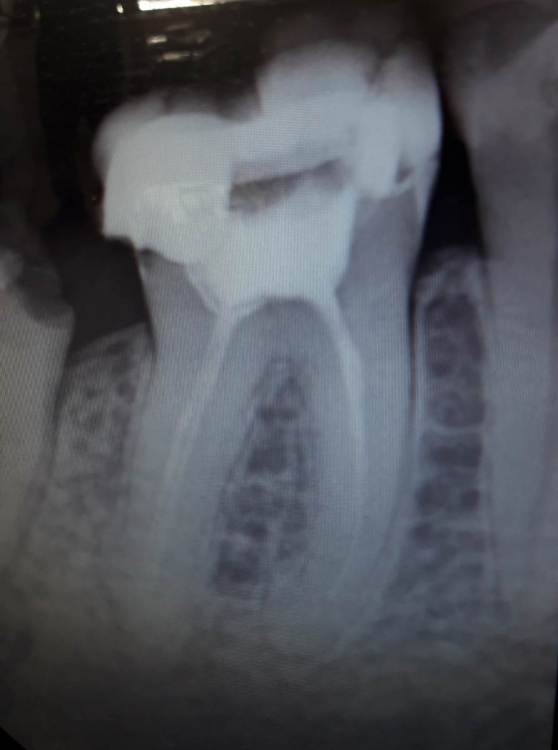

Gammy Опубликовано 28 июля, 2021 Поделиться Опубликовано 28 июля, 2021 (изменено) Здравствуйте. За качество снимков сразу извиняюсь, в клинике куда ходила, только сфотографировать с экрана дали. Нижняя 7ка, старая большая пломба, откололся кусок зуба, пока не болит. На консультации сначала сказали выбирать: 1. коронка, но не ясно как выйдет, ещё надо пытаться лечить (вроде как нерв умер и идет воспаление). 2. удалять и имплант. А потом стали склонять к импланту, надежнее и результат более предсказуем. Вот я и озадачилась Есть смысл с таким зубом бороться за коронку? И 6ка, тоже разваливается, нервы удалены давно. По снимку реально сказать, можно ли коронку делать или удалять и имплант? Изменено 28 июля, 2021 пользователем Gammy Ссылка на комментарий

chervoncevdaniil Опубликовано 29 июля, 2021 Поделиться Опубликовано 29 июля, 2021 Я бы оба пробовал перелечить,по 7 лучше сделать КТ 2 1 Ссылка на комментарий